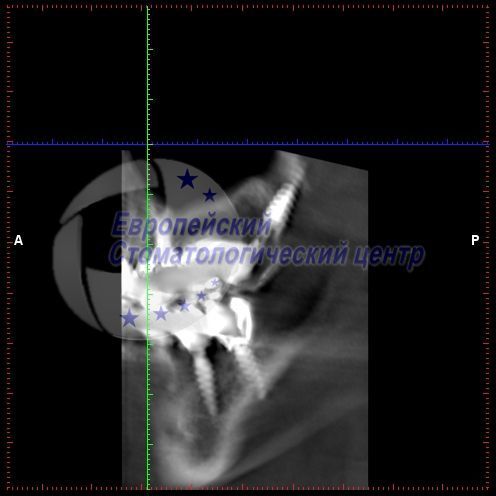

Якщо є поруч анатомічні утворення, то за допомогою 3D планування їх можна обійти. Спеціалізацією нашої стоматології якраз і є маніпуляція без нарощування кісткової тканини. Ми встановлюємо штучні одиниці в обхід анатомічним структурам у тверду мінералізовану кістку.

- 3D центр;